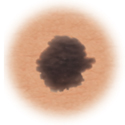

Moles (nevi)

Small skin marks caused by pigment-producing cells in the skin. Moles can be flat or raised, smooth or rough, and some contain hair. Most moles are dark brown or black, but some are skin-colored or yellowish. Moles can change over time and often respond to hormonal changes.

Most moles are benign and no treatment is needed. Some benign moles may develop into skin cancer (melanoma). See below for signs.

Distinguishing benign moles from melanoma

Certain moles are at higher risk of changing into malignant melanoma, a form of skin cancer. Large moles that are present at birth and atypical moles have a greater chance of becoming cancerous. Finding cancerous skin growths early is important because that’s when treatment is most likely to be effective. Removing the melanoma through surgery seems to work best as the treatment. When a melanoma is diagnosed early, surgery usually removes all the cancer.

Use this ABCDE chart below to help you see changes in your moles at the earliest stages. The warning signs include: